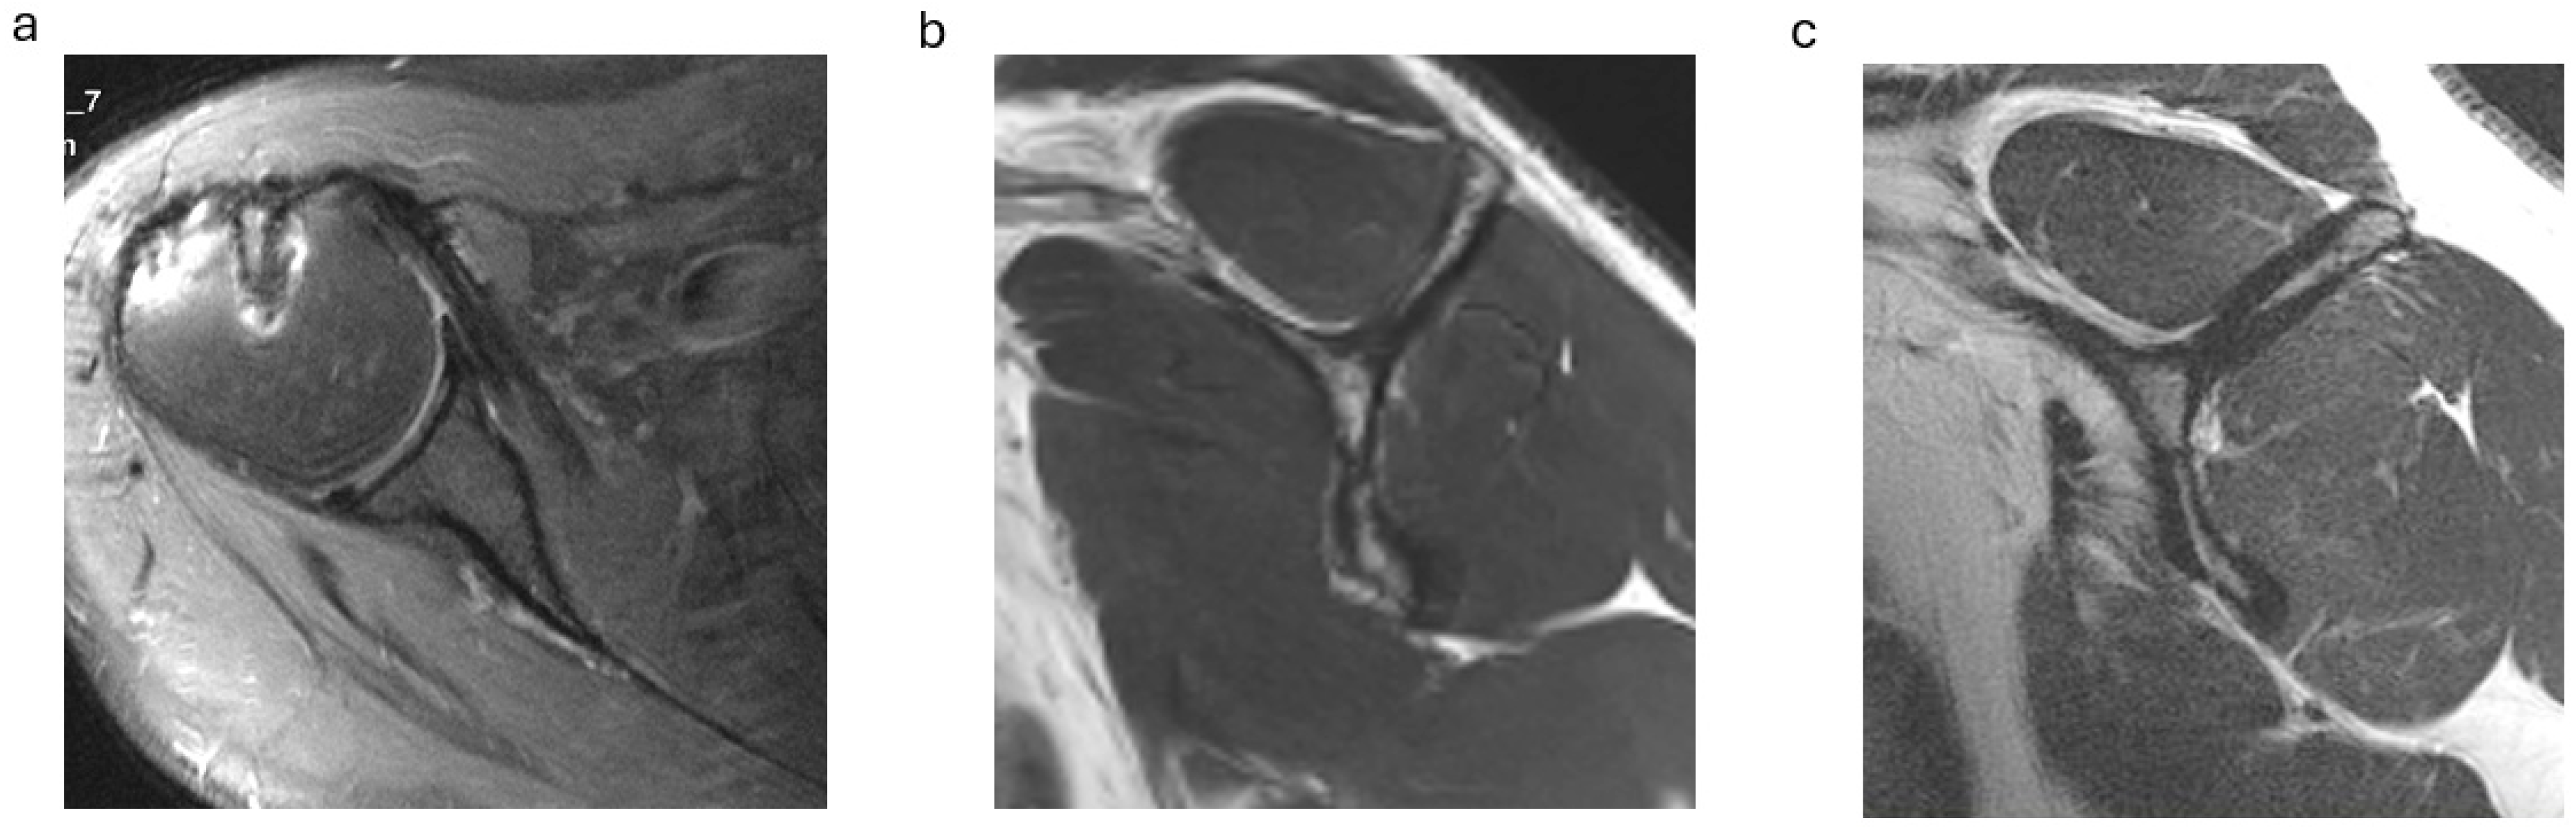

For tendon mobilization, footprint preparation and anchor insertion, additional anterior and anterolateral portals were established, and the subscapularis tendon edge was identified from the lateral portal (Figure 2). In the case of non-retracted tears of the subscapularis tendon, the connection to the transverse ligament was released for tear confirmation. Retracted tendons were released from scar tissue at the scapular neck, the upper tear margin and anterior scarring to the subcoracoid bursa. The mobilized tendon edge was then pulled with traction sutures to the footprint area at the lesser tuberosity.

Following footprint preparation, one to three anchors, depending on the size of the lesion, were placed from inferior to superior at the lesser tuberosity, and the tendons were fixed with knots after perforation with a suture passer (Figure 2, Video S1).

Figure 2. (ac). Arthroscopic subscapularis repair technique. (a) Arthroscopic tendon identification and release of a type 3 subscapularis tear. (b) Arthroscopic tendon mobilization to the lesser tuberosity. (c) View from posterior after tendon refixation at the footprint.